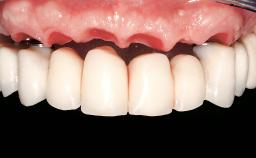

Two dental implants are placed in the same surgical session. The case concludes with the presentation of the final fixed dental prosthesis with a distal cantilever unit.

The 1-year follow-up radiographs demonstrate successful sinus floor elevation and stable bone crest levels around both implants, leading to a favorable long-term prognosis of the implant-supported prosthesis.